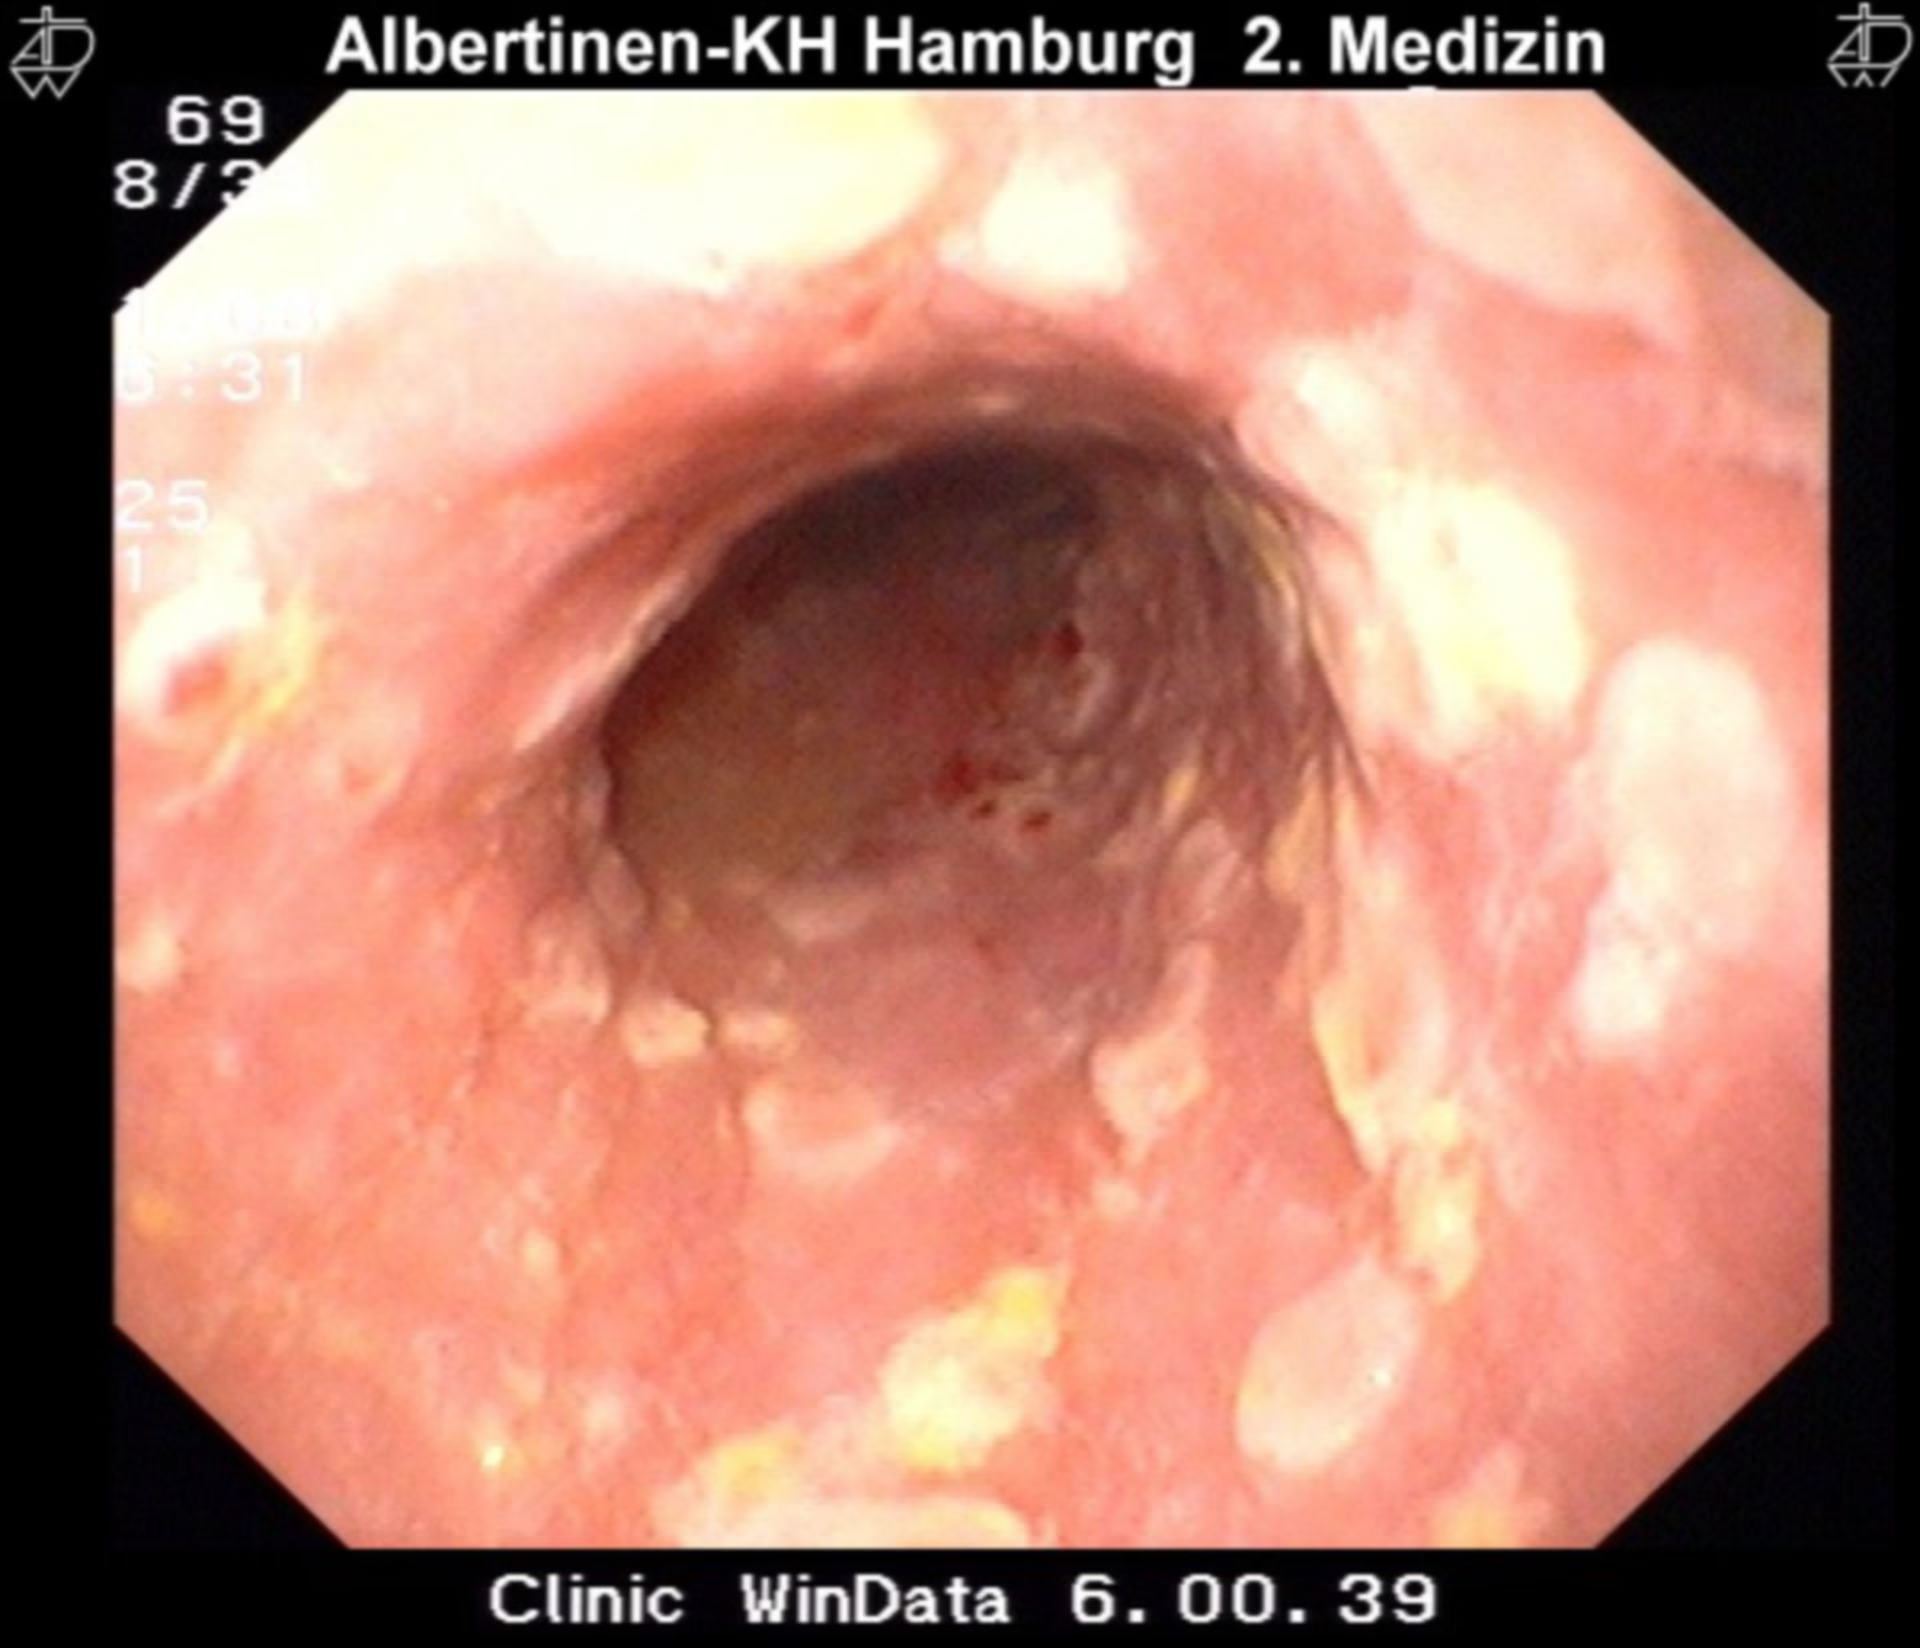

Endoskopi (gastroskopi): Ved denne procedure føres et tyndt, fleksibelt rør med et kamera (et endoskop) ned gennem munden til spiserøret. Dette giver lægen mulighed for direkte at inspicere slimhinden. Ved herpes esophagitis vil lægen typisk se flere små, velafgrænsede, "udstansede" sår. Sårene kan være spredt ud over hele spiserøret, men ses oftest i den midterste eller nederste tredjedel.

| Herpes Esophagitis | Herpes Simplex Virus (HSV) | Små, velafgrænsede, "udstansede" sår med normal slimhinde imellem. |